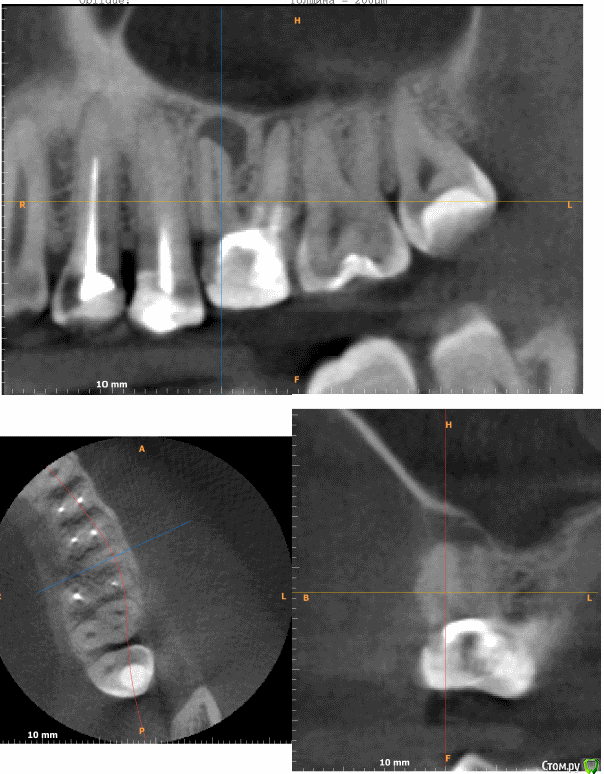

Mihail_op Опубликовано 14 сентября, 2017 Поделиться Опубликовано 14 сентября, 2017 Здравствуйте, подскажите, пожалуйста, На КТ у корня видна киста (?). Снаружи десны, ближе к щеке немного выпирает этот бугорок.Зуб не болит, не шатается, киста никак не проявляет себя, бугорок тоже не болит. Врач после панорамного снимка (до КТ) предложил вырвать и поставить имплант. Есть шанс вылечить зуб? Приложил скриншот.небольшое видео из программы файлы КТ https://yadi.sk/d/2YnW9hg33MojCv(.dcm) Ссылка на комментарий

red_butler Опубликовано 14 сентября, 2017 Поделиться Опубликовано 14 сентября, 2017 Есть шанс вылечить зуб? основное на что нужно смотреть это объем оставшихся твердых тканей и возможность протезирования зуба. Я бы рекомендовал начать с диагностического препарирования - убрать пломбу, если зуб можно восстановить коронкой, то преступать к лечению периодонтита. Но Вы должны понимать, что гарантии на успех не будет, а в финансовом плане это сопоставимо с имплантацией. 2 Ссылка на комментарий